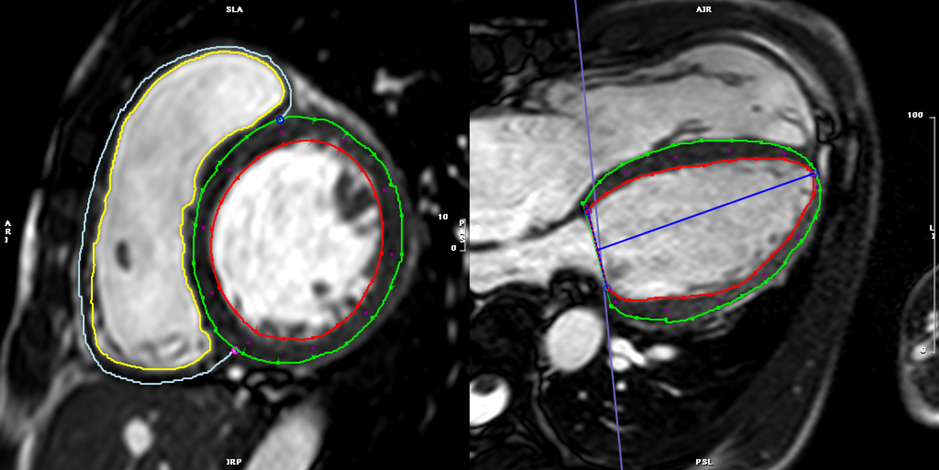

3. bSSFP左室短軸像シネMRI(Fig. 3

Pediatric Cardiology and Cardiac Surgery 40(4): 260-271 (2024)

Fig. 3 Top: Planning of the short axis image plane parallel to the mitral valve in the 4 chamber long axis plane (left) and 2 chamber long-axis plane (right). Bottom: 18 short axis cine slices shown from base (top left) to apex (bottom right).

シネMRIの撮影の項で記載したように,左室長軸に沿って心臓全体を連続する単軸像で撮影し評価する(Fig. 3).

心室全体をカバーする単軸像すべてに対して,心外膜と心内膜の輪郭をトレースすることで,内腔容積を算出する.短軸像を積み重ねることで心室全体の容積が算出できる.拡張末期と収縮末期の両時相において内腔容積を計測することで,拍出量や駆出率などが算出される(Fig. 8).

Fig. 8 Left ventricular (LV) and right ventricular (RV) chamber quantification. For LV chamber quantification, the endocardial (red) and epicardial (green) contours are delineated in diastole (left) and systole (right) in a stack of short axis slices that cover the whole left ventricle. For RV chamber quantification, the endocardial (light blue) and epicardial (yellow) contours are delineated. Papillary muscles and cordal tissues are excluded from the LV and RV volume.